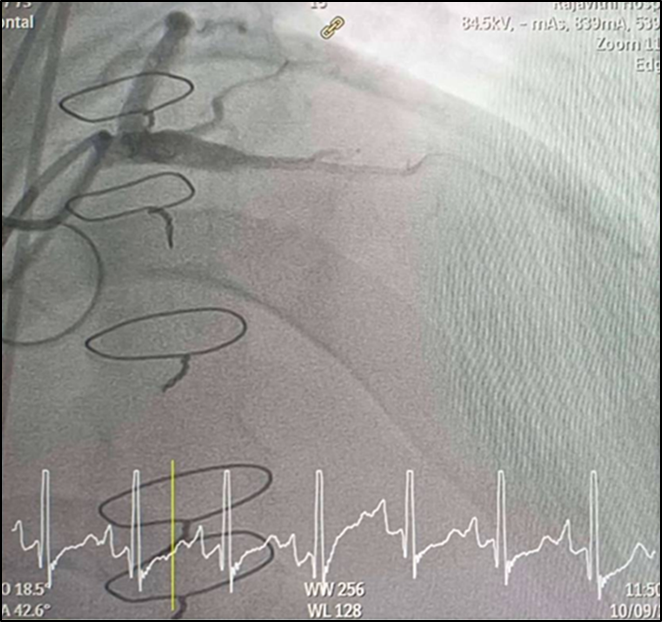

CAG was performed with right femoral approach with JL 4.0/7 Fr, JR 4.0/6 Fr diagnostic catheter showedRight dominantLM : mild irregular, non significant stenosis.LAD : total occlusion mLAD.LCx : mild irregular, non significant stenosis.RCA : non significant stenosis.

Inserted Sion wire and thrombuster to LAD revealed multiple red clots.SC balloon 2.0 x 15 mm, then 2.5 x 15 mm, was inflated at mLAD up to 12 atm. IVUS insertion to LAD revealed vessels’ size LM 5-5.5 mm, pLAD 4-4.5 mm, mLAD 3-3.5 mm with intraluminal thrombus, dLAD 2.75-3 mm. Multiple inflations were done at mLAD with SC balloon 2.5 x 15 mm. After multiple SC balloon inflations, the CAG revealed slow flow phenomenon. Then, the operator performed thrombus aspiration, multiple SC balloon 2.0 x 15 mm inflation and gave IC integrillin 3.4 ml. The final angiogram was acceptable result. The anticoagulant was given after CAG. Chest pain was subsided and hemodynamic parameters remained stable. EKG recorded after angiography showed resolution of ST elevation at V1-3. Later, the patient was discharged with warfarin. The Aortomitral intervalvular fibrosa repair surgery was planned due to embolic complication.